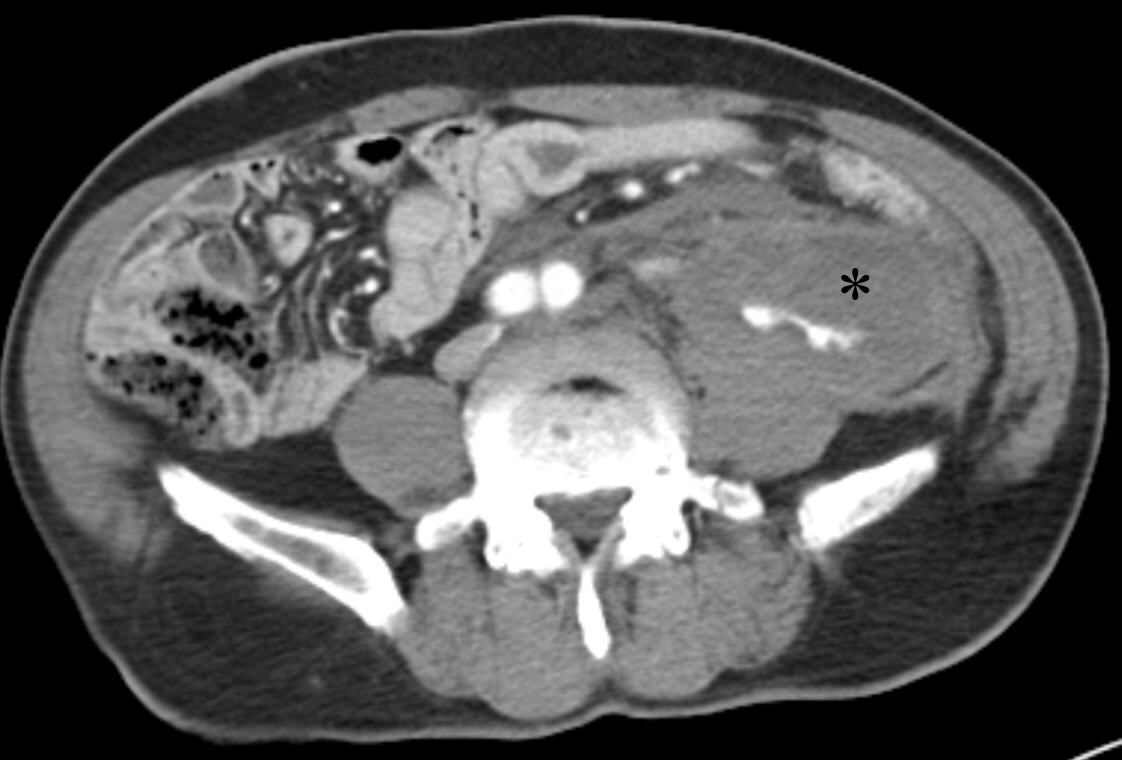

Following the procedure, the patient’s blood pressure normalized. One month later, a delayed-phase abdominopelvic CT demonstrated embolic material tracking along the course of the left ureter. Notably, when the retroperitoneal hematoma was large, the left ureteric artery appeared to originate at the 12 o’clock position; however, as the hematoma decreased, the origin of the artery was observed to shift to the 3 o’clock position (

Fig. 3). During the three-month follow-up period, the patient developed distal ureteral stenosis, which was suspected to result from the ureteric artery embolization. The patient is currently under urological outpatient follow-up with a double-J stent in situ.

Fig. 3.Follow-up CT after hematoma reduction shows the embolized left ureteric artery (arrow) as a hyperdense structure due to the presence of embolic materials. With the hematoma resolved, the artery appears to originate laterally.